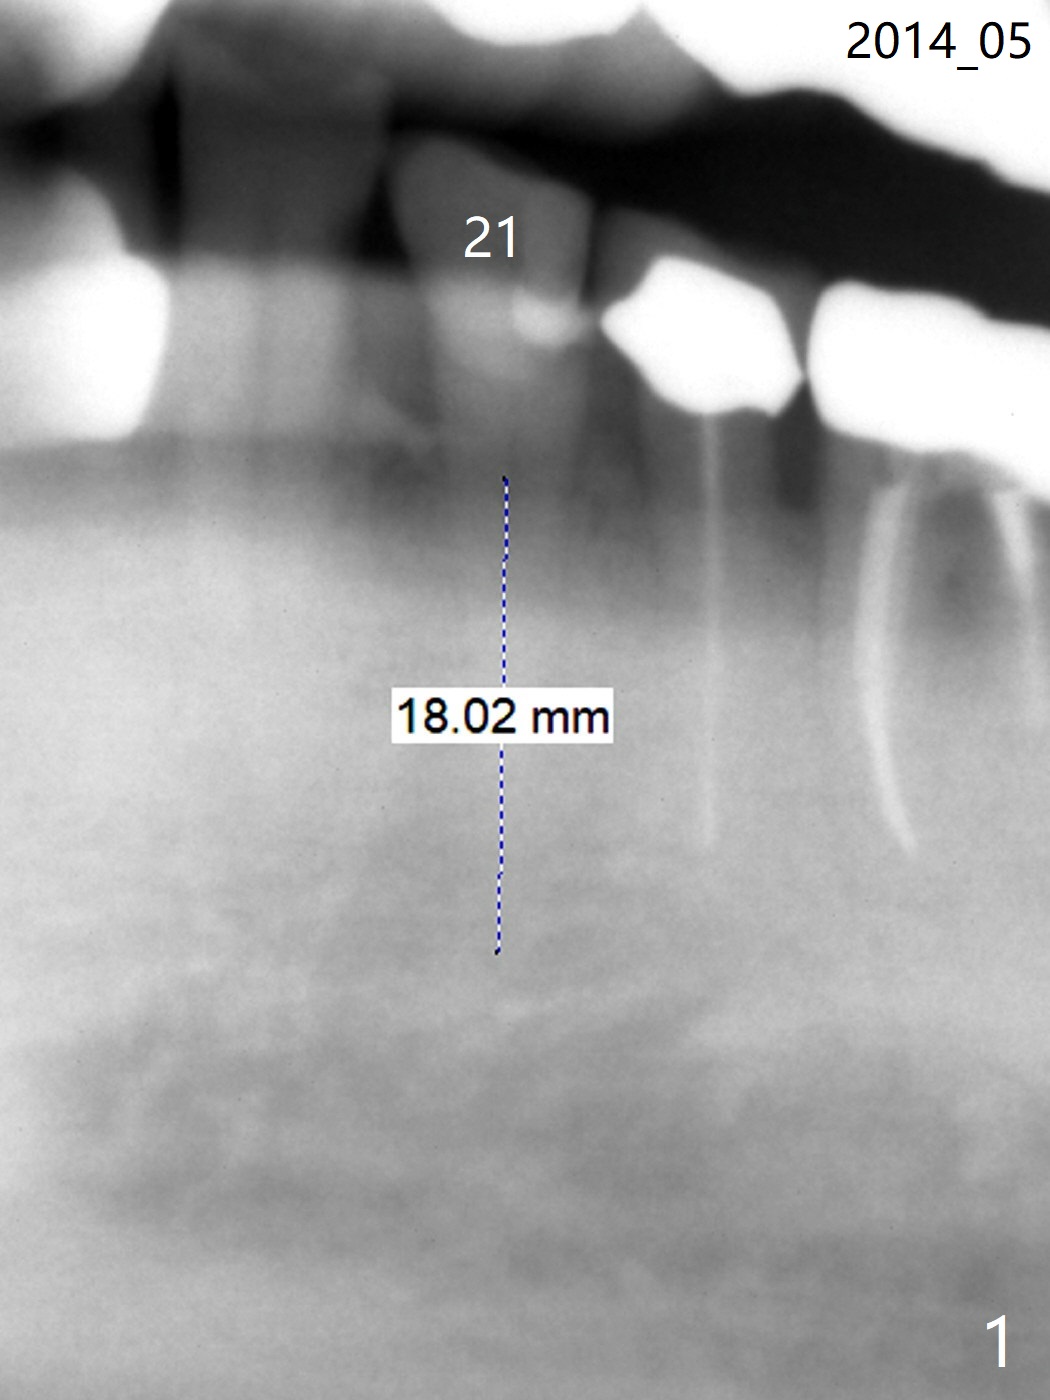

A 88-year-old man breaks the tooth #21 after RCT and post (Fig.1-3). Place a long SM implant for early final restoration, since he is a bruxer. The diameter of the implant will be 3.8-4.5 mm (Fig.2). Place the implant in the middle of the oval socket. Prepare endo ice for #23 before composite (Fig.3).